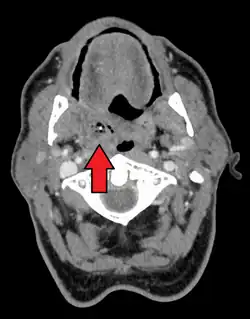

Absceso periamigdalino

El absceso periamigdalino es una acumulación de material infectado alrededor de las amígdalas palatinas.[2][1] El absceso periamigdalino generalmente se debe a una infección por varios tipos de bacterias. A menudo sigue a una faringitis estreptocócica. Por lo general, no ocurren en personas que se han sometido a una amigdalectomía. El diagnóstico generalmente se basa en los síntomas. Se pueden realizar imágenes médicas para descartar complicaciones.

Diagnóstico

Se suele descubrir al inspeccionar la orofaringe (garganta) presentando hinchazón en un lado y en el paladar. La úvula puede estar desplazada.[8]

Para confirmar el diagnóstico se pueden realizar pruebas complementarias:

- Tomografía computarizada